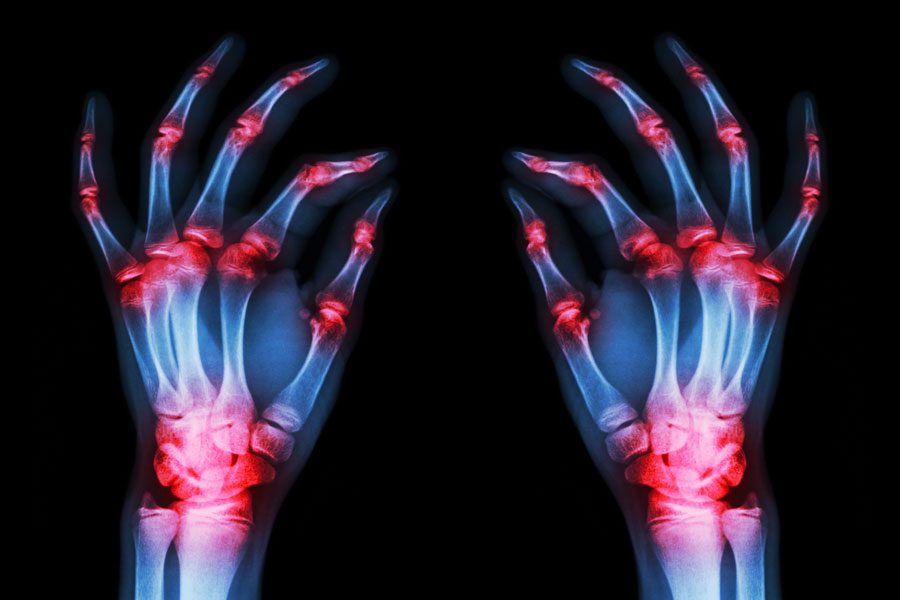

La articulación se ve hinchada, caliente y enrojecida. Puede afectar a una o varias articulaciones, y a menudo de forma simétrica (por ejemplo, en ambas manos).